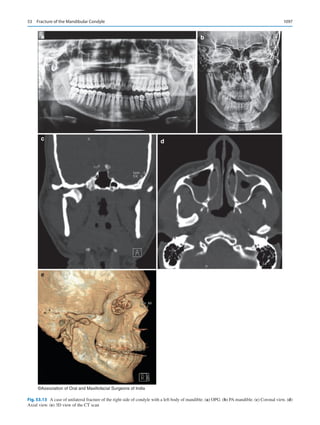

including cleft lip and palate.

Schmidt’s observations and predictions suggest that the

diseases and conditions that are the mainstay to our profes-

sion will alter significantly in the future. Laboratories in

Boston are very close to creating a template stem cells con-

struct that will replace dental implants with naturally grown

teeth. A dental caries vaccine is pending worldwide use.

How will these fundamental changes alter the practice of

our specialty in the future?

Super specialization within the specialty is bound to hap-

pen. Attendees of the annual sessions of the British